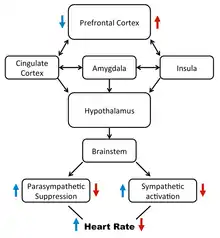

The neurovisceral integration is a model of HRV that views the central autonomic network as the decision maker of cognitive, behavioral and physiological regulation as they pertain to a continuum of emotion.[15] The neurovisceral integration model describes how the prefrontal cortex regulates activity in limbic structures which act to suppress parasympathetic nervous system (PSNS) activity and activate sympathetic nervous system (SNS) circuits.[16] Variation in the output of these two branches of the autonomic system produces HRV[17] and activity in the prefrontal cortex can hence modulate HRV.[18]

HRV is the measure of the inconsistent gaps between each heartbeat and is used as an index for different aspects of psychology.[15] HRV is reported to be an index of the influence of both the parasympathetic nervous system and the sympathetic nervous systems.[19] Different aspects of psychology represent the balance of these two influences. For example, high HRV is shown proper emotion regulation, decision-making, and attention, and low HRV reflects the opposite.[19] The parasympathetic nervous system works to decrease heart rate, while the SNS works to increase heart rate, and this is important because it applies to the different psychological states mentioned above.[15] For example, someone with high HRV may reflect increased parasympathetic activity, and someone with low HRV may reflect increased sympathetic activity.[20]

Previous research has suggested that a large part of the attention regulation is due to the default inhibitory properties of the prefrontal cortex.[19] Top-down processes from the prefrontal cortex provide parasympathetic influences, and if for some reason, those influences are active, attention can suffer.[19] For example, researchers have suggested that HRV can index attention. For example, a group of researchers found that groups with high anxiety and low HRV have poor attention.[24] In line with this research, it has also been suggested that increased attention has been linked to high HRV and increased vagus nerve activity.[19] The vagus nerve activity reflects the physiological modulation of the parasympathetic and sympathetic nervous system.[15] The activity behind the prefrontal cortex and the parasympathetic and sympathetic nervous system can influence heart activity. However, people are not all affected the same. A systematic review of HRV and cognitive function suggested that resting HRV can predict individual differences in attentional performance.[25] Even in psychological concepts such as attention, HRV can index individual differences. Furthermore, HRV has been able to index the role of attention and performance, supporting high HRV as a biomarker of increased attention and performance.[26] Both emotion and attention can shed light on how HRV is used as an index for decision making.